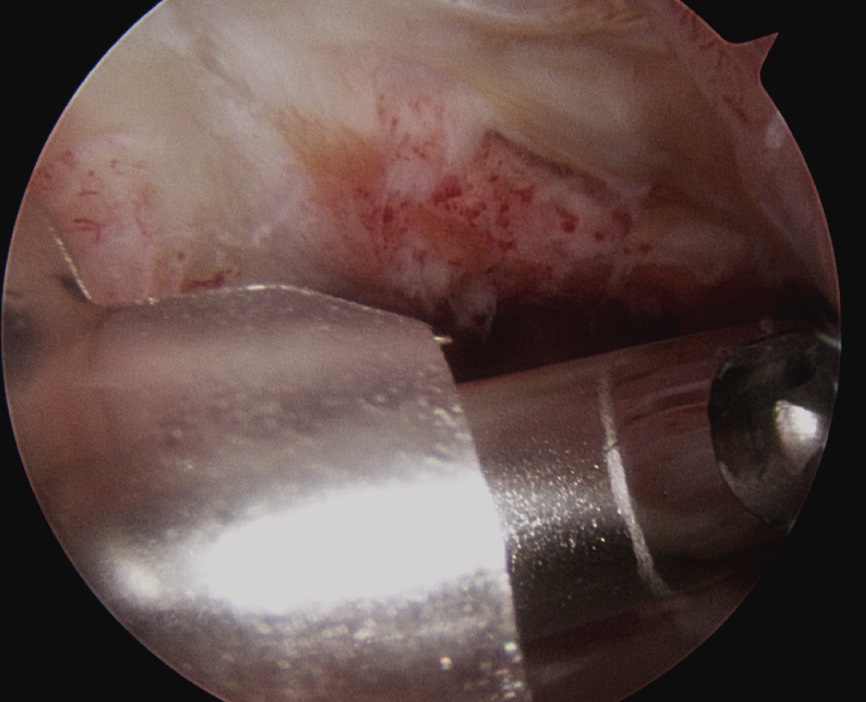

- debride base of Hill Sachs to bleeding bone

Anchor insertion into Hill Sachs lesion